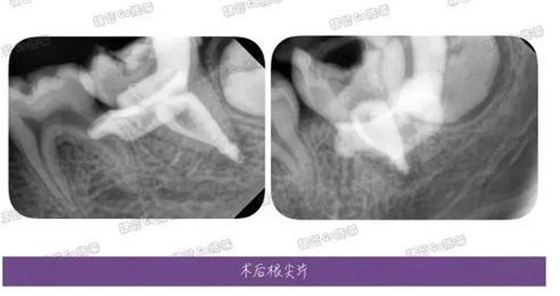

完成充填后的多角度根尖片,檢查根充效果,之前有幾個(gè)病例糊劑超填得明顯,所以做了一定的改正。

這例看來是控制得稍微好點(diǎn)了,繼續(xù)努力~